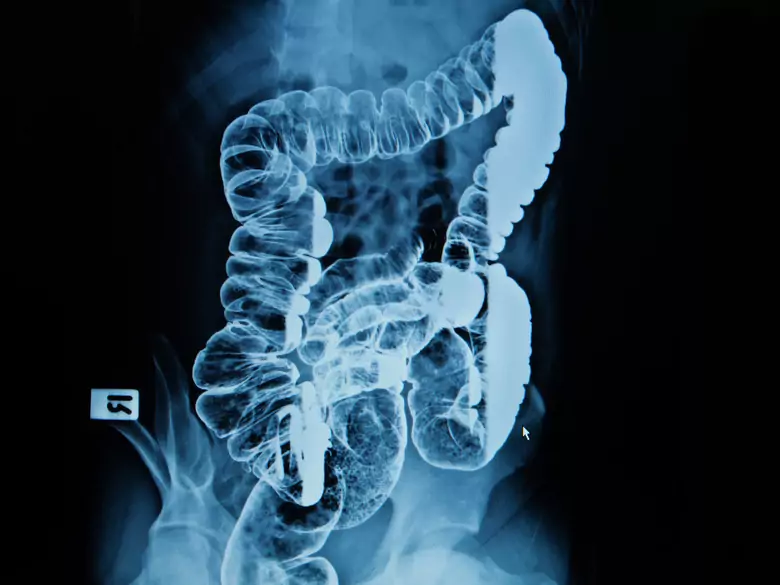

Cancer colorectal - causes, symptômes, diagnostic, traitement

Examen des intestins